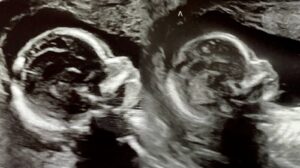

Hamileliliğinin 8’inci haftasında kontrole gittiğinde ikizleri olacağını öğrendi. Ancak tuhaf bir durum gözlendi. 32 yaşındaki Bayan Hatcher’in her iki rahminde de bebek vardı. Hemşire doktoru çağırdı ve hekim, inanabilmek için ultrasound görüntüsünü defalarca izledi. Evet gerçekten de her iki rahimde de fetus bulunuyordu.

Uzmanlara göre uterus didelphys olarak adlandırılan söz konusu durumda çifte rahimli kadınların genellikle bir rahmi işlevsel oluyordu. İki rahimde de fetüs oluşmasına milyonda bir rastlanıyordu.